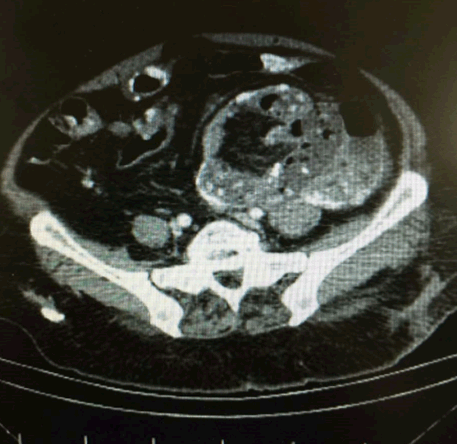

A 60-year-old female patient was admitted to the emergency service and presented with abdominal pain. Symptoms such as total constipation, nausea and vomiting were present for three days. She had had similar history of these symptoms previously and she had been hospitalized because of those symptoms. At that time, laboratory and imaging studies revealed no pathological finding one year ago. She had history of hypertension. Abdominal examination revealed abdominal distension and a palpable mass in her upper left quadrant. Laboratory studies were normal. Plain abdominal X-ray showed that there are air-fluid levels in small intestines (Figure 1). Abdominal CT revealed dilatation of small intestines and internal herniation (Figure 2). With these results explorative laparotomy was performed which showed a fixated membranous structure encapsulating all of the intraabdominal organs and not allowing to explore intraabdominal organs. The diagnosis was sclerosing encapsulated peritonitis according to explorative laparotomy. Adhesiotomy was partially applied. Physical examination was normal with spontaneous intestinal motility and normal defecation during the postoperative follow-up period. The patient was discharged from the hospital following uneventful course and appeared well in the outpatient visits.

Figure 2: Intestines are enveloped in a sac giving the appearance of volvulus according to computed tomography.

Sclerosing encapsulated peritonitis is a rare clinical condition and its etiology is obscure. The underlying conditions of sclerosing encapsulated peritonitis are multifactorial [2]. It is classified into two categories as idiopathic and secondary. Generally, there are colicy abdominal pain, nausea, vomiting and sometimes a palpable mass in the midline of the abdomen. Preoperative diagnosis requires a high index of clinical suspicion. Generally, diagnosis of sclerosing encapsulated peritonitis is made with laparotomy [3][4]. In the present case, there was a patient with abdominal pain, left upper quadrant mass and obstructive findings which resulted in explorative laparotomy. In the surgical treatment of sclerosing encapsulated peritonitis, adhesiolysis or adhesiotomy is enough, unless a nonvital intestinal segment is present which requires resection [5]. The retrospective evaluation of the same radiologist revealed a sac encapsulating intestines in the postoperative period. The preoperative mass was in fact the sac enveloping the intestines to the side.s